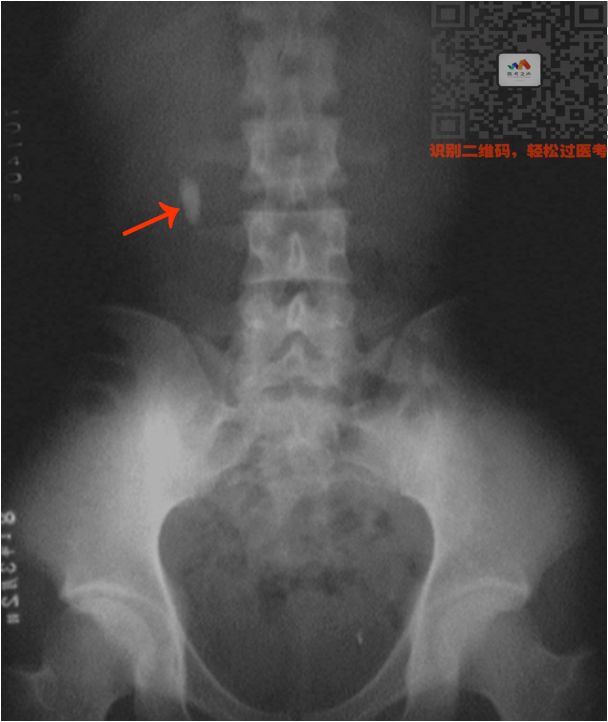

③ 泌尿系统阳性结石

病史:两侧腹部绞痛

特点:

肾和输尿管里面单个或成串的高密度影

看到两侧腹部有白色的圆点

就选肾结石/输尿管结石

看到下腹部的,就选膀胱结石

看图

(双肾结石)

(输尿管结石)

(膀胱结石)